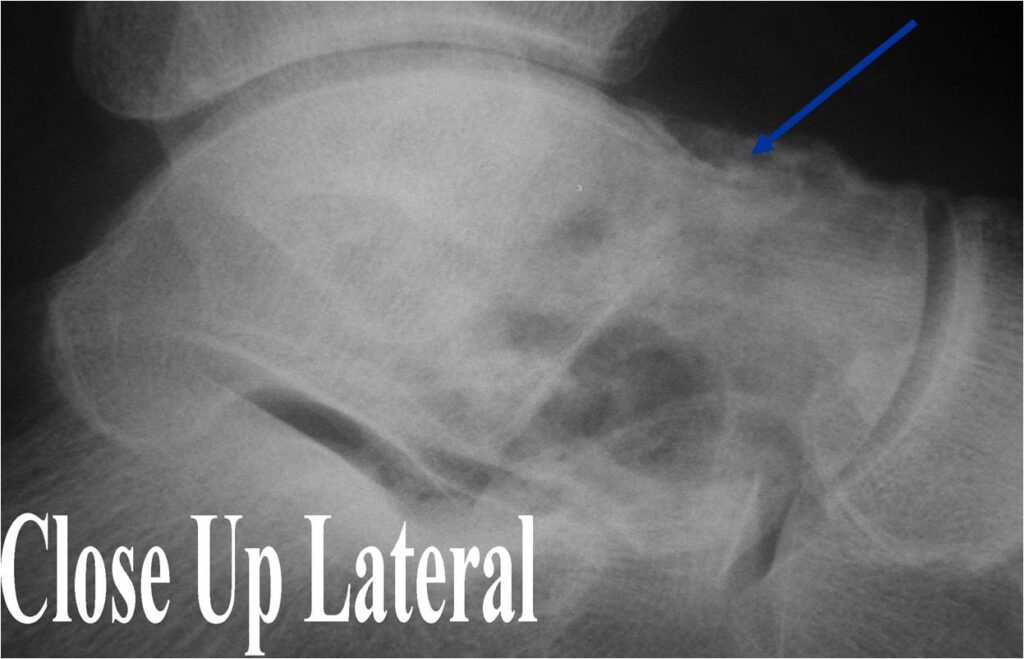

General Information Enchondroma is a benign indolent intramedullary hyaline cartilage neoplasm Accounts for 10% of all benign osseous tumors Limited growth, most lesions are less than 5 cm in maximal dimension Bones grow from a cartilaginous growth plate that...